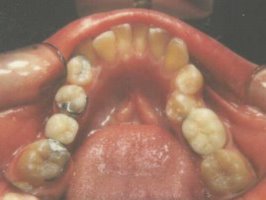

This page

shows a bonded (Maryland) bridge. You can see where the metal wings are

bonded to the tongue side of the natural teeth. The nice thing about a

bonded bridge is that you do not have to sacrifice much tooth enamel,

however, these bridges are subject to coming out and must be recemented

occasionally. |